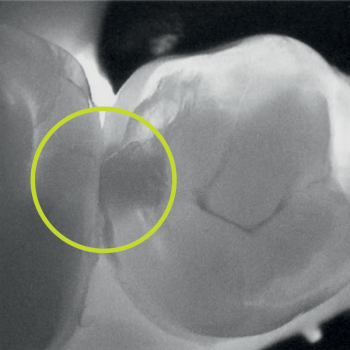

Cracks

Fluorescence mode

“The presence of cariogenic plaque revealed by the red fluorescence indicates that the lesion is active… it indicates that the surface is at risk of lesion development and progression.” — Abdelaziz, M. (2023)

Transillumination and Fluorescence as the foundation of a caries management plan allow clinicians to monitor the early lesion activity and progression without the need for irradiation.